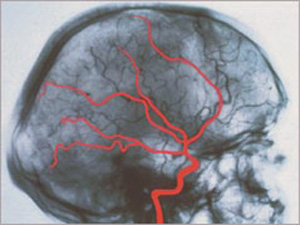

Egy agy röntgenképe

Az agyhalál visszafordíthatatlan, tehát azonos az egyén halálával hagyományos, köznapi értelemben véve. Az agy - azaz a nagyagy, kisagy és az agytörzs - működésének teljes és visszafordíthatatlan megszűnése. Az agyfunkciók, mint például a fájdalomérzékelés, a gondolkodás, a légzés irányítása, az anyagcsere-folyamatok szabályozása végérvényesen elvesznek. Ugyanez a helyzet az agy vérellátásával is. S bár a testet - a szervezet alapfunkcióit, és a transzplantálható szerveket - gépekkel még életben lehet tartani, de ez esetben - ellentétben a kómával - teljességgel kizárható, hogy az agy irányító funkciói és az eszmélet valaha is visszatérnek.